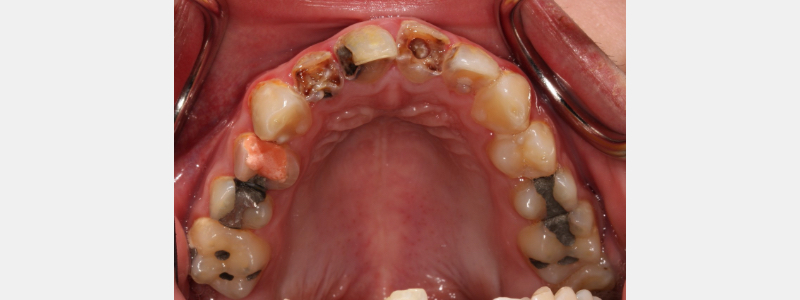

SDF can be a useful tool for conservative management of dental caries in specific clinical scenarios. Patients who have limited access to dental care, have medical or behavioral concerns that make traditional operative dentistry an extreme challenge, and have rampant dental caries can benefit from the utilization of silver diamine fluoride.

After SDF has been applied, the solution starts to kill the bacteria that have caused the carious lesion. Over a few weeks, the initial lesion will harden due to remineralization of the tooth structure.

As this occurs, the carious lesion will become darker and jet-black. The dentin in this dark, arrested carious lesion is more resistant to attack from carious bacteria than sound, unaffected dentin.

Since this dark lesion may present as an esthetic dilemma, it is advised to inform patients of the staining that SDF can cause and to have an informed consent form reviewed by the patient or their guardian prior to application of SDF.